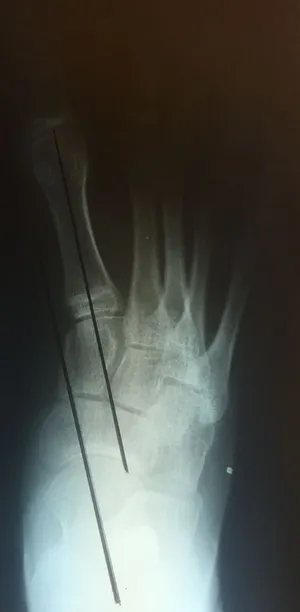

Below are x-rays of a foot pre-operatively (left) where the black line indicates and plantarflexed (downward directed) talus bone and post-surgical repair with a subtalar joint implant and lenthening of the calf muscle which allows the calcaneus (heel bone) to set underneath the talus and the implant keeps the talus from subluxing off the calcaneus and now the talus is more inline with the front of the foot (right).